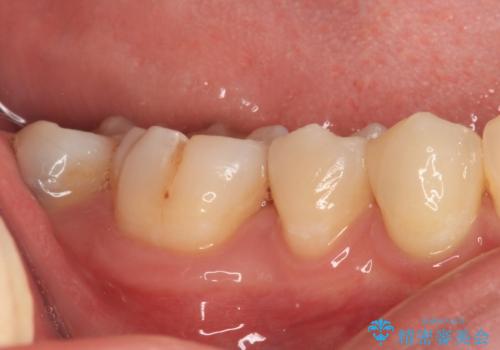

- 奥歯に頻繁に物が挟まるとのことで来院された患者様です。

最近ものが挟まりやすくなったり、冷たいものがしみるようになったりといった症状があり、診査したところ、むし歯や歯質の欠損、不適修復物などが認められました。

精度の高いセラミックインレーによる修復治療を行うこととしました。